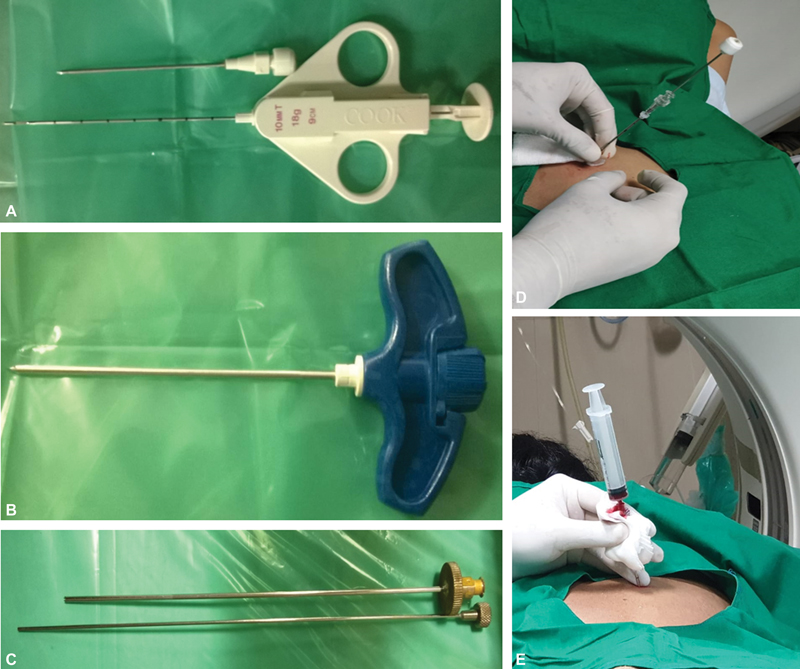

Techniques

Coaxial technique-A guide needle, larger than the biopsy needle (typically 9–19G), is advanced under image guidance, reaching the edge of the target. The inner stylet is removed, the biopsy gun is introduced into the lesion, and multiple specimens are taken with a single puncture. This may prevent tumor cells from seeding along the needle tract by re-inserting the inner stylet of the coaxial needle before the removal compared to the non-coaxial method. The coaxial technique reduces procedural time and procedure-related pain (by reducing repeated punctures) and also decreases the rate of complications ([Fig. 5]).

| Figure 5:(A) Coaxial biopsy system showing biopsy needle and gun. (B-C) Murphy's needle and ackerman's used for bone biopsy. (D-E) Post biopsy clot embolisation of biopsy tract in lung biopsy.

| Figure 5:(A) Coaxial biopsy system showing biopsy needle and gun. (B-C) Murphy's needle and ackerman's used for bone biopsy. (D-E) Post biopsy clot embolisation of biopsy tract in lung biopsy.